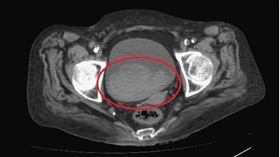

可怕!腎臟長癌了 大肚男:沒啥不適

定期健康檢查之所以重要,一大原因在於癌症等重大疾病在...

養身婦無痛血尿2周 檢查已經第3期

新竹57歲劉姓婦人平時吃的都很養身,但2週以來陸續出...

血尿以為一般感染 尿檢異常揪出魔王

發炎、感染、結石是造成血尿的常見原因,另一個不可不警...